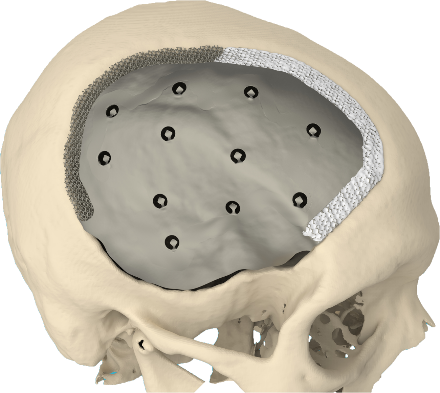

Se utilizaba a manera de cuchillo con mango de madera haciendo incisiones en cruz sobre el hueso para ocasionar una trepanación rectangular, además fueron hechas con otros instrumentos más delgados practicando perforaciones que luego se articulaban entre sí para conseguir un colgajo óseo; el defecto óseo que quedaba era recubierto por una lámina de oro (craneoplastia).

Se observa un crecimiento exponencial en tecnologías, pero también las mejorías en la neuroanestesia, instrumental, materiales protésicos, técnicas quirúrgicas, así como subespecialidades estrechamente relacionadas a la neurocirugía